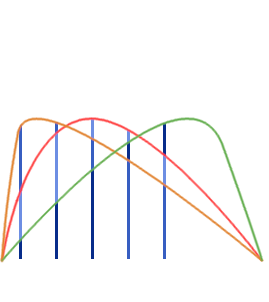

Multi Echo (ME-fMRI)

- Single Echo (SE): during fMRI acquisition we collect the signal once per TR at a certain TE to obtain one timeseries per voxel

-

Multi Echo (ME): we collect the signal multiple times at different TEs to obtain n timeseries per voxel

Multi Echo (ME-fMRI)

- Single Echo (SE): during fMRI acquisition we collect the signal once per TR at a certain TE to obtain one timeseries per voxel

-

Multi Echo (ME): we collect the signal multiple times at different TEs to obtain n timeseries per voxel

Optimal combination

For each voxel and TR, we can Optimally Combine the echo volumes with a weighted sum based on their contribution to \( T_2^{\star} \)

In this way, spatial CNR and tSNR are maximised and the signal can be recovered in areas of drop-out

Posse et al. 1999 (Magn Reson Med)

ME-ICA

Assuming monoexponential decay, we can express the

signal percentage change as:

\[ S_{SPC} \approx \Delta\rho - TE \cdot \Delta R_2^{\star} + n \quad where \enspace R_2^{\star} = \frac{1}{T_2^{\star}} \]

This let us differentiate BOLD-related (\(\Delta R_2^{\star}\)) from non-BOLD related (\(\Delta\rho\)) changes

Kundu et al. 2012 (NeuroImage)

If we apply ICA, we can fit the timeseries of the components to either sub-models and automatically classify them